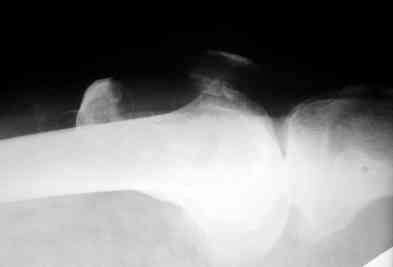

В приложении фото пациента с переломом надколенника 3 месячной давности. После мобилизации отломков, 4 главой мышцы бедра и полного разгибания голени оставался диастаз между костными фрагментами в 2 см. В связи с этим наложили модуль из аппарата Илизарова - 2 опоры и 2 спицы (в верхнем полюсе надколенника и верхней трети большеберцовой кости). Очень медленно (в течение 15 минут) путем накручивания гаек на стержнях растянули 4 главую мышцу бедра и устранили диастаз. Аппарат демонтировали и выполнили остеосинтез <стягивающей петлей>. Через 6 месяцев фиксаторы удалены. Автор данного <хирургического трюка> профессор из Австрии Vilmos Vecsei (<Гений ортопедии>, 2004, № 4, С. 94-95). Ваш случай не совсем идентичный по давности травмы и малой величине дистального отломка, но описанный <трюк> может оказаться полезным и при выполнении операции, которую рекомендует Джолдас.